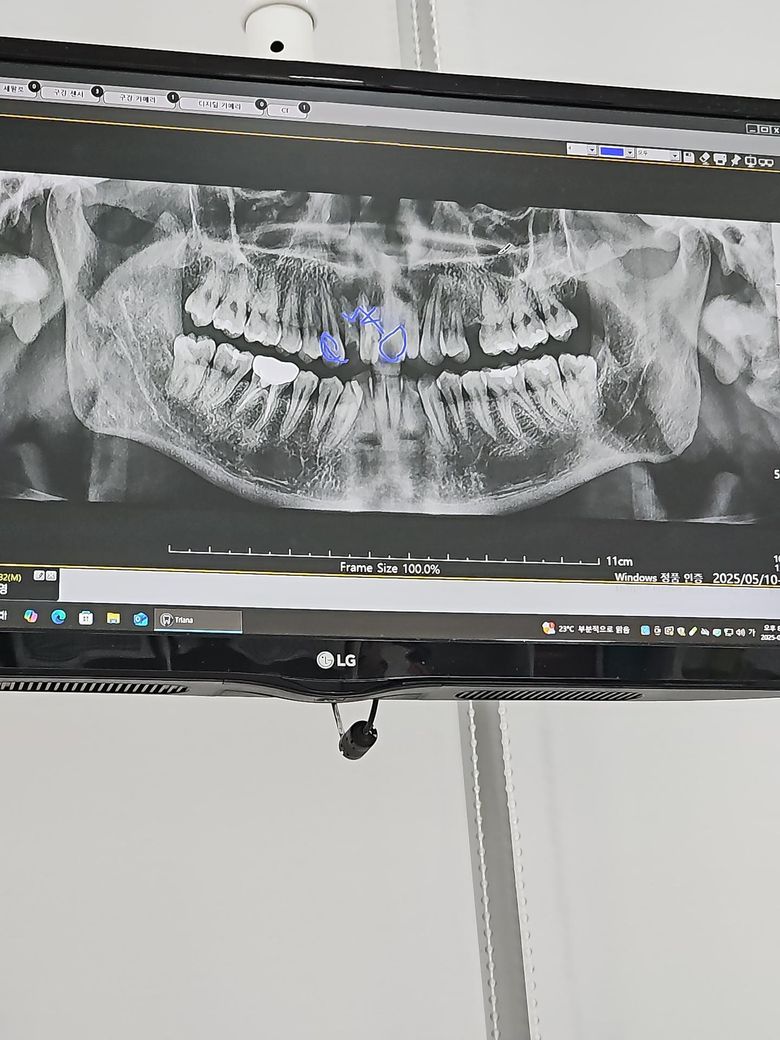

우선 앞니옆 이빨이깨져서 갔는데 잇몸이 너무 안좋아 앞니 ,앞니옆이빨이 염증이 심해 우선 바로 못해서 방법 제시했는데 의사쌤이 이2~4개 발치후 브릿지 지나 /아직 젊어서 염증 치료후 이빨 2개 에 크라운 방법 제시했습니다/근디 크라운치료 앞니빨은 가격이 크다고 90만원 앞니옆 60만원 이라해서 140~160만원 나온다고 합니다 해당가격이 맞는지 확이부탁드립니다

• 1번 째 사진